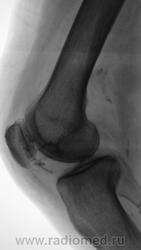

Грибовидная солитарная остеохондрома бедра у 28-летнего мужчины. Оперативное и гистологическое подтверждение диагноза.(Рейнберг).

Определяется "грибовидное" образование на ножке с мелкобугристой поверхностью, крупинчатым пятнистым рисунком,обусловленым наличием костных островков, веерообразных пучков и перегородок лежащих на светлом фоне хряща

Остеохондрома.